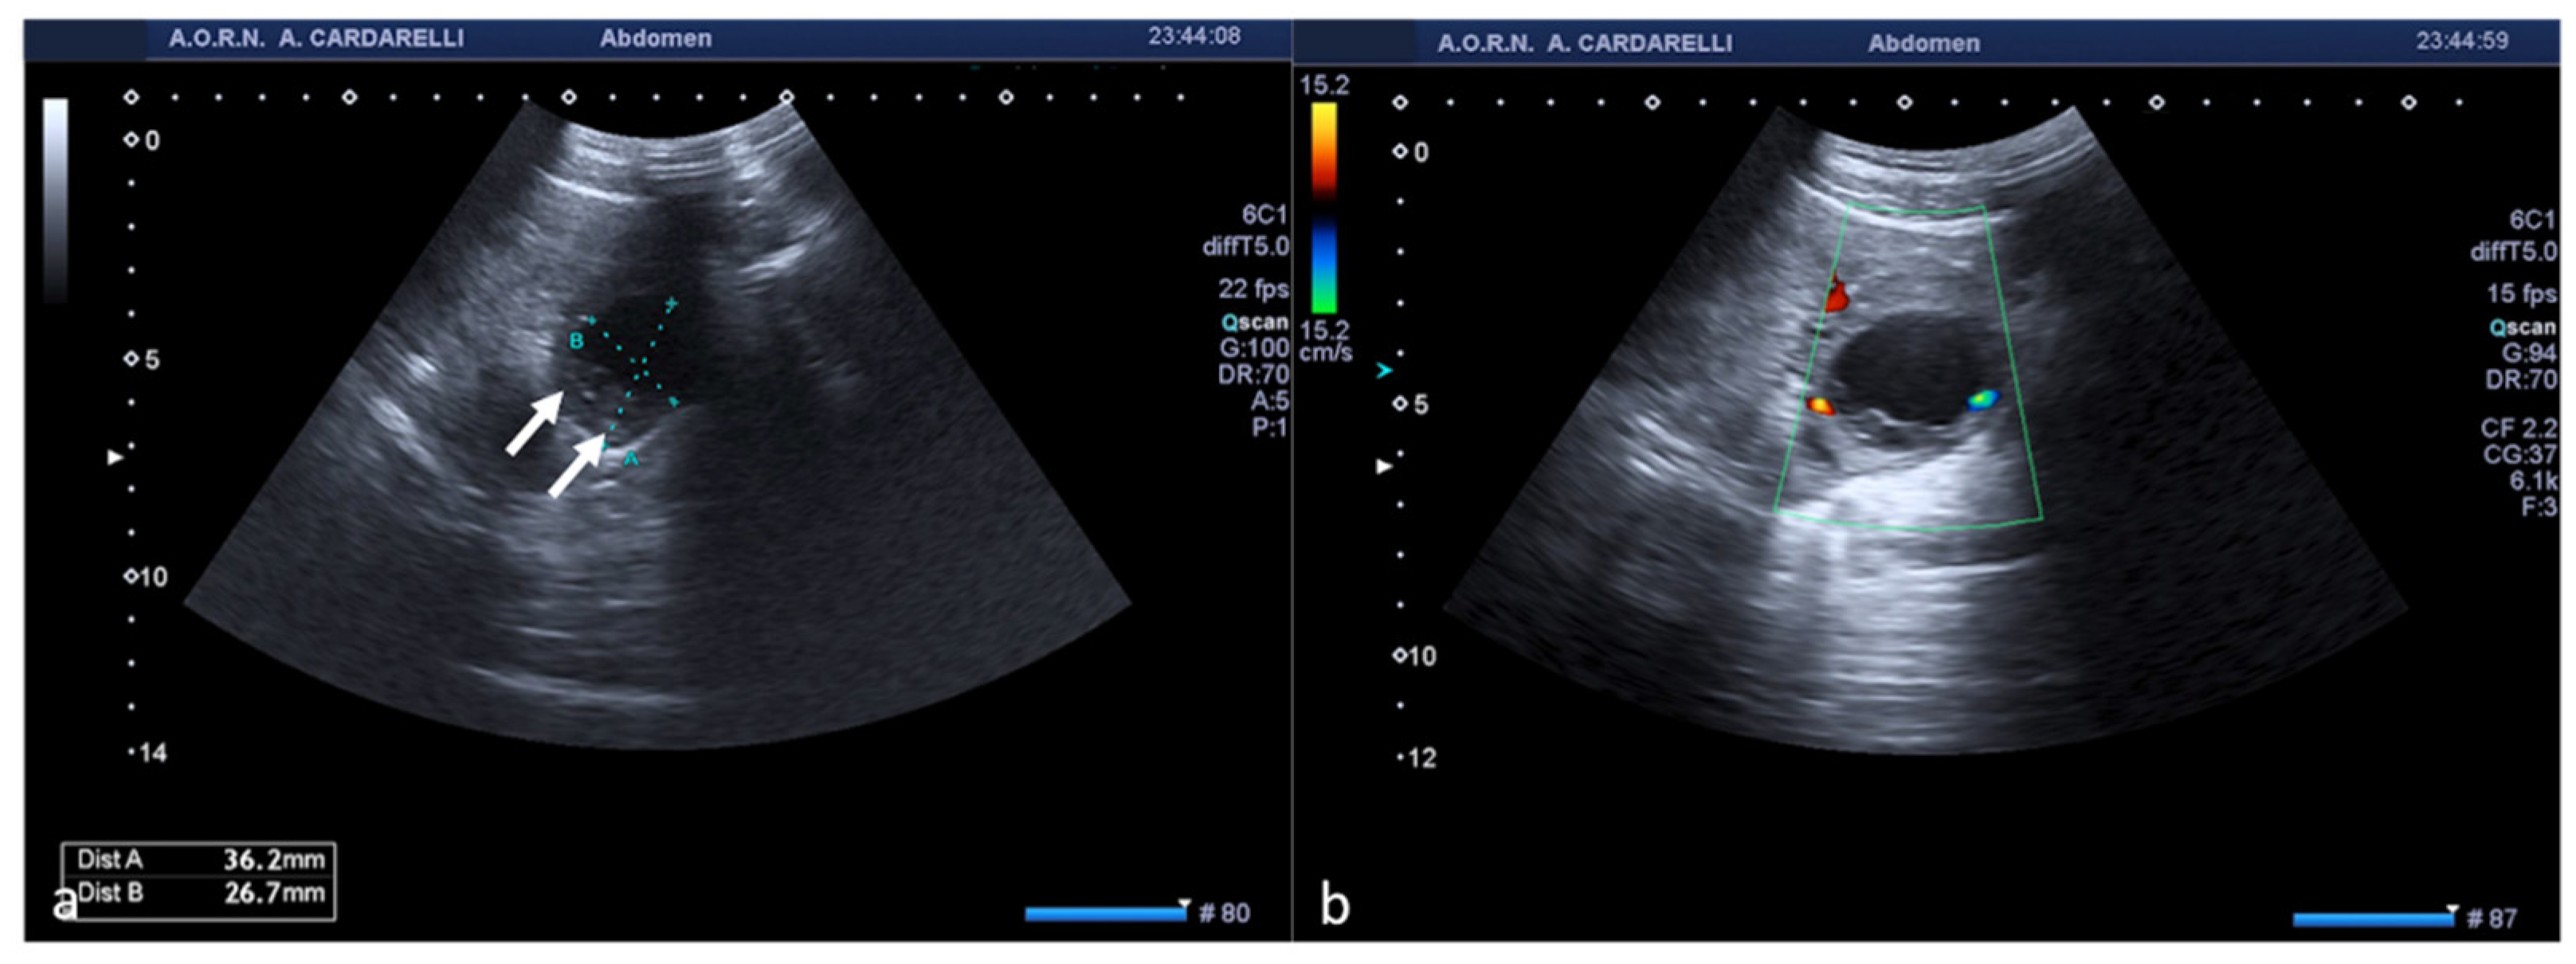

Figure 13. Fibroid degeneration. Axial (a) TSA–US scan shows a heterogeneous uterine mass ((a), caliper) with cystic areas inside ((a) arrow). On colour Doppler (b) no vascular signal is detected.